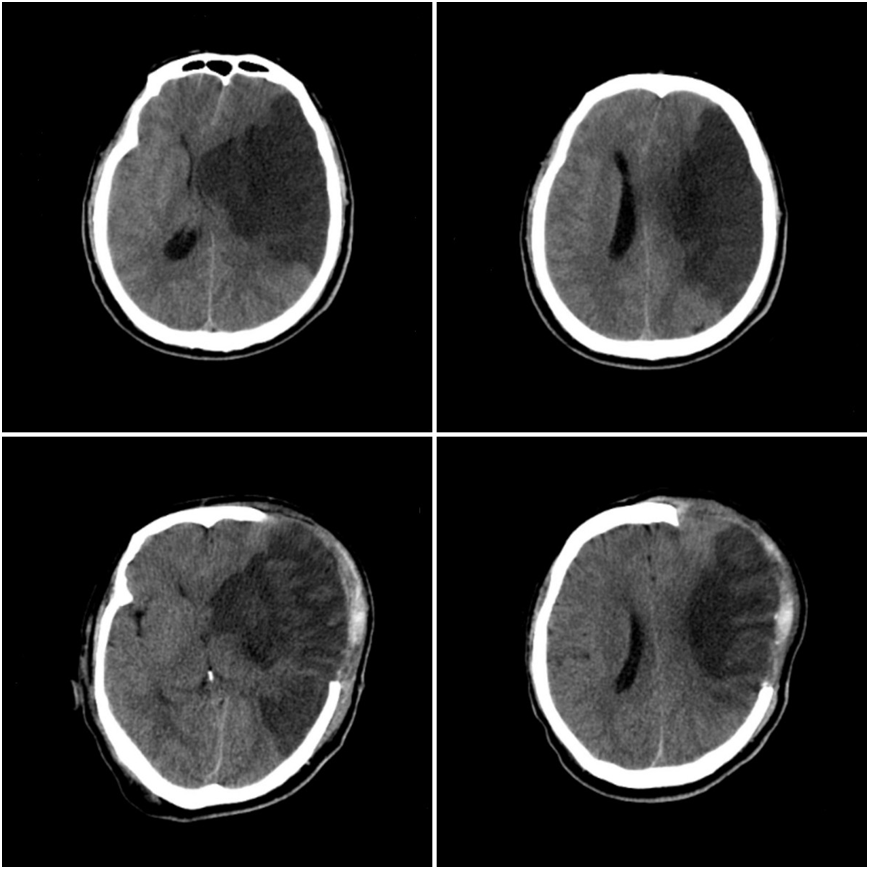

该患者因“突发意识不清伴右侧肢体活动不灵7小时”收治于烟台山医院北院神经内一科。入院后颅脑磁共振检查提示大面积脑梗死(图1),北院神经内一科王英主任医师带领团队给予患者抗栓、降脂、改善侧支循环治疗。该病病情变化快,入院第二天在发现患者意识状态改变后,立即为患者复查颅脑CT,提示脑梗死较以前加重,中线结构位移明显(图2),患者被转到北院神经外科继续接受治疗,医生为其做了颅骨去骨瓣减压术+颞肌贴敷术。术后颅脑CT提示,中线结构移位较术前好转,脑室受压较以前减轻(图2)。

图1:术前颅脑MRI可见左侧颞叶大面积梗死灶,左侧大脑中动脉闭塞。

图2:次日复查颅脑CT提示脑水肿较前明显,左侧侧脑室受压,中线结构右侧移位。术后复查颅脑CT示中线结构移位较前好转,无出血等并发症。